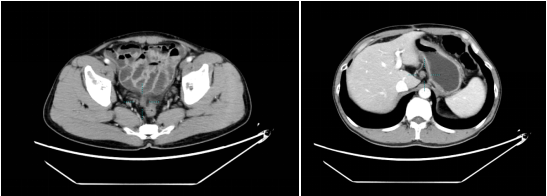

我院2021.04.01胸部增强CT:1. 双肺多发小结节。腹盆腔增强CT:1. 胃癌术后,腹膜不规则增厚,考虑转移(2.0cm*1.7cm)。

腹部CT示:胃癌术后,腹膜不规则增厚转移较前退缩(1.4cm×0.9cm)。

腹部CT示:1. 胃癌术后,胃壁增厚较前变薄、腹膜转移灶较前略退缩(1.2cm×0.9cm),盆腔少量积液;2. 肝胃间隙稍大淋巴结(1.3×1.4cm)。